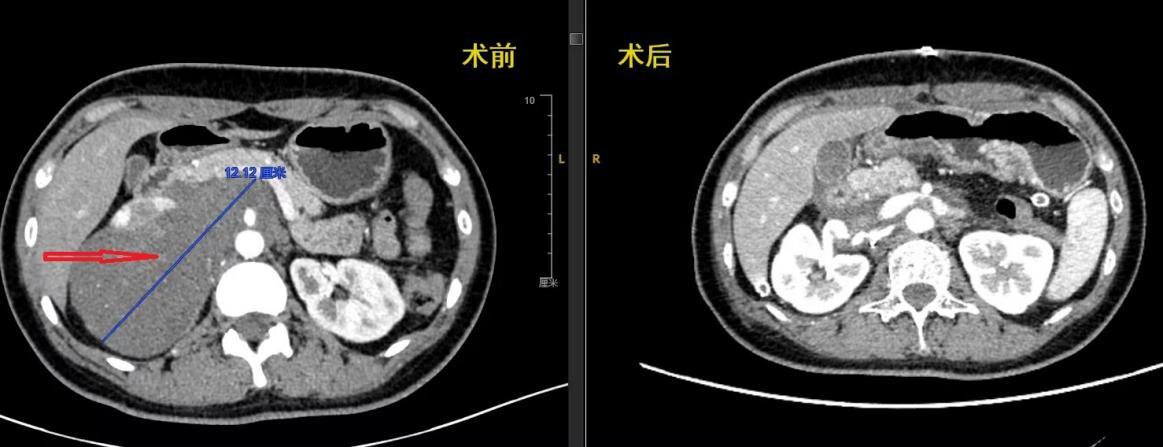

患者术前术后CT影像对比图

尽管术前进行了充分准备,手术过程仍然充满挑战。术中冰冻病理验证了良性节细胞神经瘤的术前判断后,考虑到肿瘤包绕多个大血管,团队采取分块切除策略。在麻醉科张欢主任团队的保障下,李雁和宋继勇将下腔静脉和肾静脉远近端分离,并预置了血管阻断带,以便及时控制术中的大出血。但下腔静脉后壁致密粘连,分离过程中仍不可避免地出现了破损,血如同决堤的大坝一样,一瞬间从下腔静脉后壁的破口处汹涌而出,淹没了术野,宋继勇迅速压迫静脉破口,并阻断远近端血流,凭借高超的血管吻合技术,使用比发丝还细的缝线将静脉进行了修补重建。肿瘤外科医师刘刚、姬忠贺、李兵、于洋轮番上台,辅助两位主任又逐步成功剥离了腹主动脉、肠系膜上动脉、腹腔干及主要分支动脉,并切除重建了受累及的纤细的右侧副肾动脉。术后影像显示肿瘤全部切除。